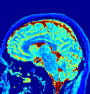

VI-A Datasets and 2D/3D acquisition parameters

Methods are tested on the Brainweb in-silico phantom (see supplementary materials), a EUROSPIN TO5 phantom (in-vitro) [50], and a healthy human brain (in-vivo). In-vitro and in-vivo data were acquired on a 1.5T GE HDxT scanner using 8-channel receive-only head RF coil. The novel adopted excitation sequence has repetitions and jointly encodes T1/T2 values using an inversion pulse followed by a flip angle schedule that linearly ramps up from to in repetitions 1-400, ramps down to in repetitions 400-600, and then stays constant to for repetitions 600-880 (see more details in [51]). Three non-Cartesian readout trajectories were tested: 2D/3D variable density spiral and 2D radial k-space subsampling patterns. Throughout we used inversion time=18 ms, fixed TR=12 ms, and TE = 0.46/2.08 ms for spiral/radial acquisitions, respectively. For the 2D/3D acquisitions we had (mm2/mm3) FOV and voxels image/tensor size, respectively. Further, the total number of interleaves for the 2D/3D spiral and 2D radial readouts were 377/48’400 and 967, respectively. Only one radial spoke (or spiral arm) was sampled at each of the 880 timeframes, resulting in aggressive acceleration (undersampling) factors 62, 252 and 262 with respect to a fully sampled 2D spiral, 2D radial and 3D spiral acquisitions, correspondingly. The total acquisition times for the 2D and 3D scans were 10:56 seconds and 9:51 minutes, respectively. For all cases coil sensitivities were computed from undersampled data using an adaptive coil combination scheme [52].

VI-E In-vivo experiments

Two sets of experiments were conducted here: first, we used the 2D and 3D acquisition sequences for scanning a healthy volunteer’s brain (real-world acquisitions). Figures 6 and 7 display the parametric maps reconstructed from 2D spiral and radial readouts. We computed the T1, T2 and proton density (PD) maps using baseline reconstruction algorithms ZF, VS, LR, FLOR, AIR-MRF and our proposed LRTV. While baselines use DM either for quantitative inference or also during reconstruction (i.e. AIR-MRF), we further compare the DM-free LRTV’s performance when cascaded to DM, KM and MRFResnet for quantitative inference. For the 3D spiral acquisitions we compared LRTV and its closest competitor VS in Figure 8. Outcomes from other tested algorithm are displayed in the supplementary materials (Figure S5). Since FLOR does not use dimensionality-reduction, our system ran out of memory during 3D reconstruction; hence results are not reported in this case.